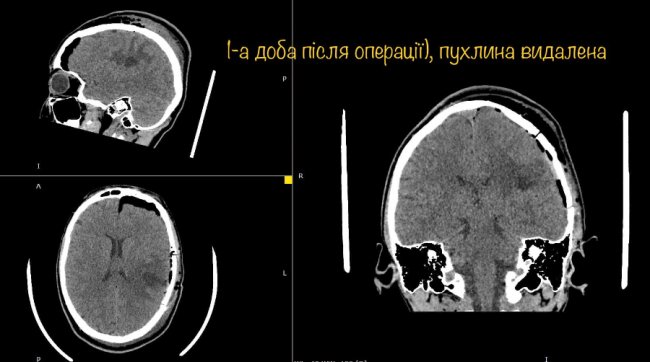

Діана вже через годину після операції вільно розмовляє, звичайно рухає усіма кінцівками і ні на що не скаржиться.